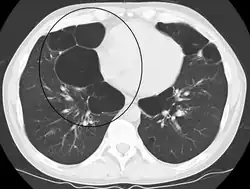

A CT scan is not routinely used except for the exclusion of bronchiectasis.[5] Pulse oximetry measurement of peripheral oxygen saturation is recommended in people with clinical signs of respiratory failure or right heart failure.[5] An analysis of arterial blood is recommended in those with a peripheral oxygen saturation of 92% or less to determine actual blood oxygen level and assess for high levels of carbon dioxide in the blood, which may have therapeutic implications such as need for non-invasive ventilation or oxygen supplementation.[10] WHO recommends that all those diagnosed with COPD be screened for alpha-1 antitrypsin deficiency.[40]